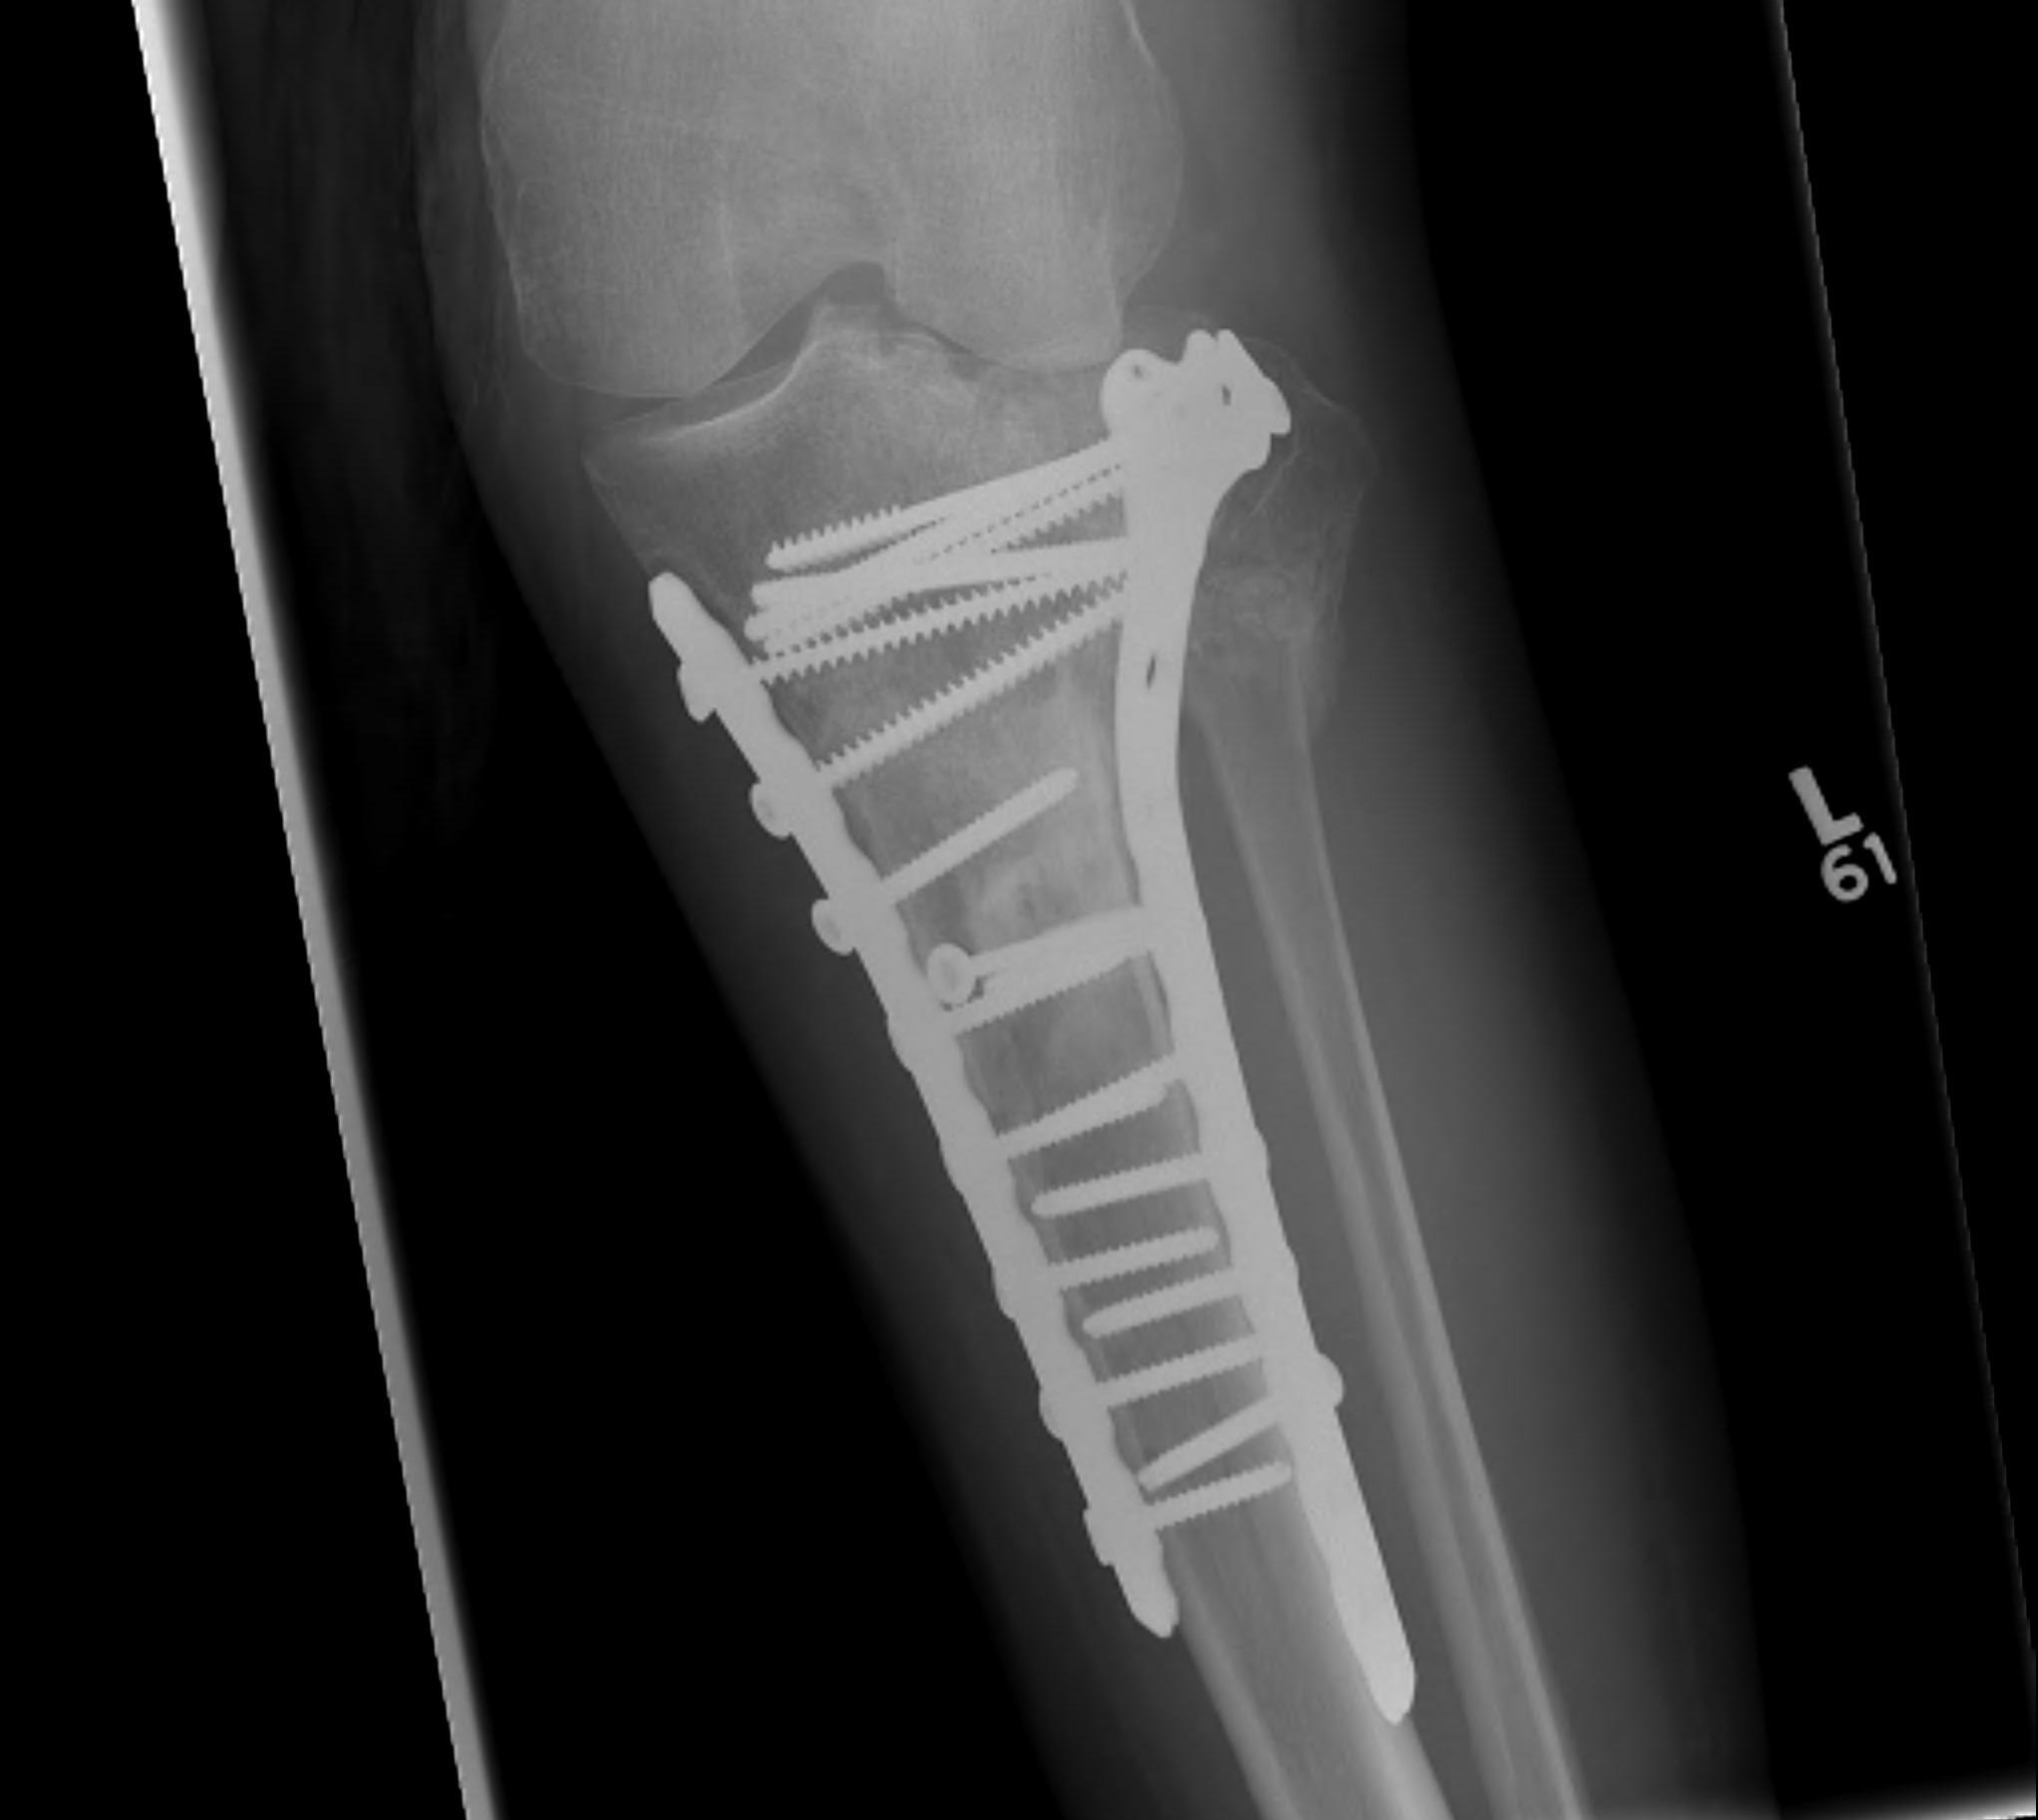

Type VI Bicondylar with Metaphyseal Fracture

Technique

- long locking plate minimally invasive with locking jig / MIPO

- proximal lag screws

- ensure correct alignment

- often use small medial buttress plate